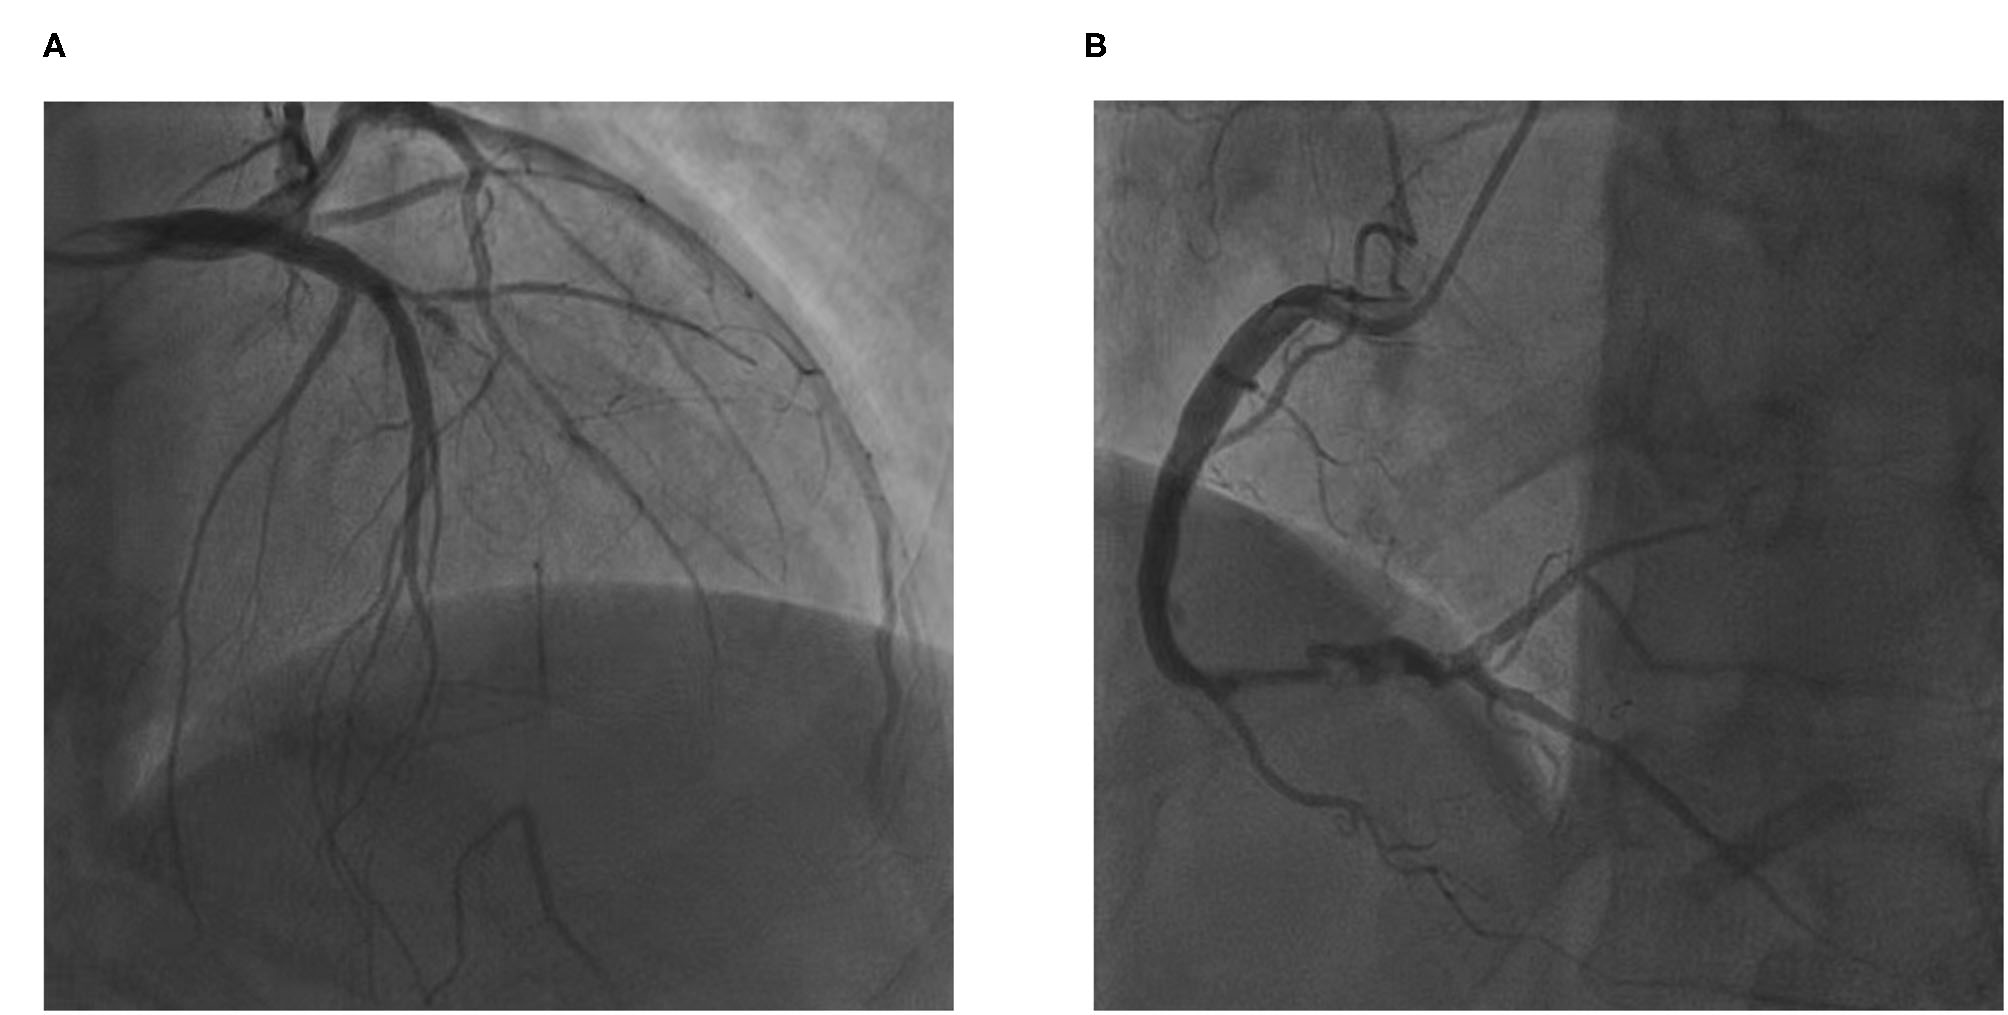

The electrocardiogram showed pathologic Q-waves in the anterior and inferior leads. Transthoracic echocardiography showed impaired left ventricular function (EF = 38%) and a dilated left ventricle (LV = 75 mm). The patient was diagnosed with coronary heart disease with unstable angina and heart failure. After receiving intensive anti-anginal and anti-heart failure medications, the patient underwent planned coronary arteriography a week later. Coronary angiography showed stent occlusion in the mid-LAD (Figure 1A) and severe in-stent restenosis in the distal RCA (Figure 1B). A proximal septal branch was supplying the distal LAD retrogradely (Figure 1A). The SYNTAX (Synergy between PCI with Taxus and Cardiac Surgery) score was 14.5.

Figure 1

The patient's coronary angiography. (A) In-stent chronic total occlusion of left anterior descending artery and a proximal septal branch supplying the distal left anterior descending (LAD). (B) Severe in-stent restenosis of right coronary artery.